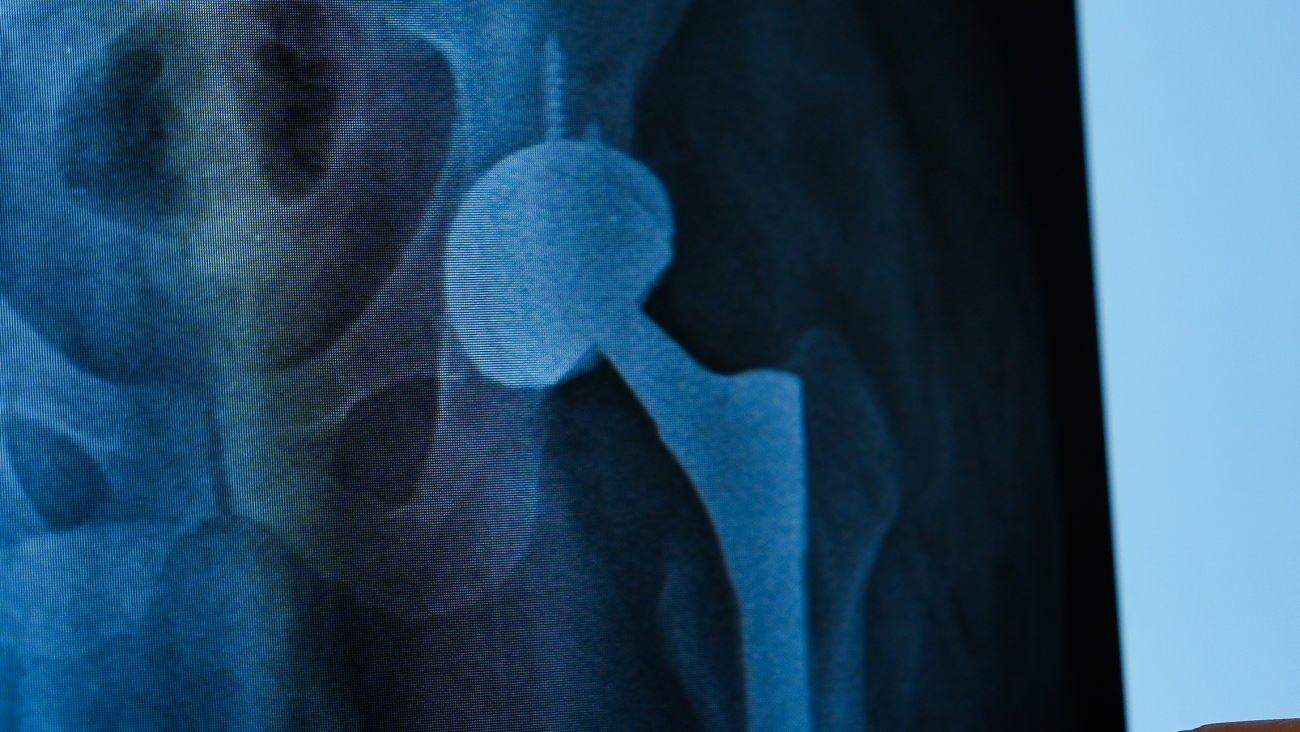

Kalça protezi ameliyatı sonrası gelişen enfeksiyon nedeniyle şiddetli ağrılar çeken Zafer Aygün, Medipol Sıhhat Grubu’nda uygulanan tek etaplı cerrahi metodu ile ağrısız bir biçimde tekrar yürümeye başladı. Prof. Dr. İbrahim Azboy’un gerçekleştirdiği tek basamaklı protez ameliyatı ile kalça enfeksiyonu tedavi edilen Aygün, “Uzun vakittir birinci kere ağrısız yürüyorum. Hayata yine döndüm” dedi.

Tekirdağ Ergene’de yaşayan Zafer Aygün için iş kazası sonrası başlayan kalça ağrıları, dört yıl boyunca bitmek bilmeyen bir sıkıntıya dönüştü. Farklı hastanelerde ameliyatlar geçirmesine karşın, kalça protezi etrafındaki enfeksiyon ve protezdeki gevşeme nedeniyle ömür kalitesi her geçen gün daha da düştü. Aygün, aradığı tahlili Medipol Mega Üniversite Hastanesi’nde buldu. Ortopedi ve Travmatoloji Uzmanı Prof. Dr. İbrahim Azboy’un uyguladığı tek etaplı kalça protezi değişimi prosedürüyle sıhhatine kavuşarak hayatına kaldığı yerden devam etti.

Tedavi süreci hakkında ayrıntılı bilgi veren Prof. Dr. İbrahim Azboy, “Hastamız daha evvel protez ameliyatı olmuş lakin protezin yerinden çıkması, akabinde gevşeme ve çökme meseleleri yaşamış. Bu komplikasyonlar üzerine ağrıları devam edince bize başvurdu. Enfeksiyon kuşkusuyla yapılan ileri testlerde kalçada ayrıyeten enfeksiyon tespit ettik. Genelde bu tip durumlarda iki basamaklı cerrahi uygulanır. Bu prosedürde iki ameliyat yapılır. Protez çıkarıldıktan süreksiz olarak kalçaya çimento konur. İki ay sonra çimento çıkarılıp yine protez yerleştirilir. Lakin biz, Zafer beyin protez enfeksiyonunu ‘’Almanya’da geliştirilen tek etaplı metotla tedavi ettik” dedi.

“Önce enfekte protez çıkarıyor. Daha sonra mekanik debridman denilen yolla enfekte dokular tesirli bir biçimde temizleniyor. Akabinde kimyasal casuslar kullanılarak iltihaplı bölge dezenfekte ediliyor. Yara süreksiz olarak kapatılıyor. Tüm setler ve gereçler dışarı çıkarılıyor. Yeni setler açılıyor. Yeni protez tıpkı seansta hastaya yerleştiriliyor. Böylelikle tek ameliyatla hastanın enfeksiyonu tedavi edilmiş oluyor. Böylelikle hasta kısa müddette ayağa kalkabiliyor, hastanede yatış mühleti kısalmış oluyor ve kalça işlevlerini kısa müddette geri kazanıyor. Nitekim, Zafer Bey de ameliyat sonrası süratle yürümeye başladı ve hastaneden kendi aracına kullanarak taburcu oldu.”